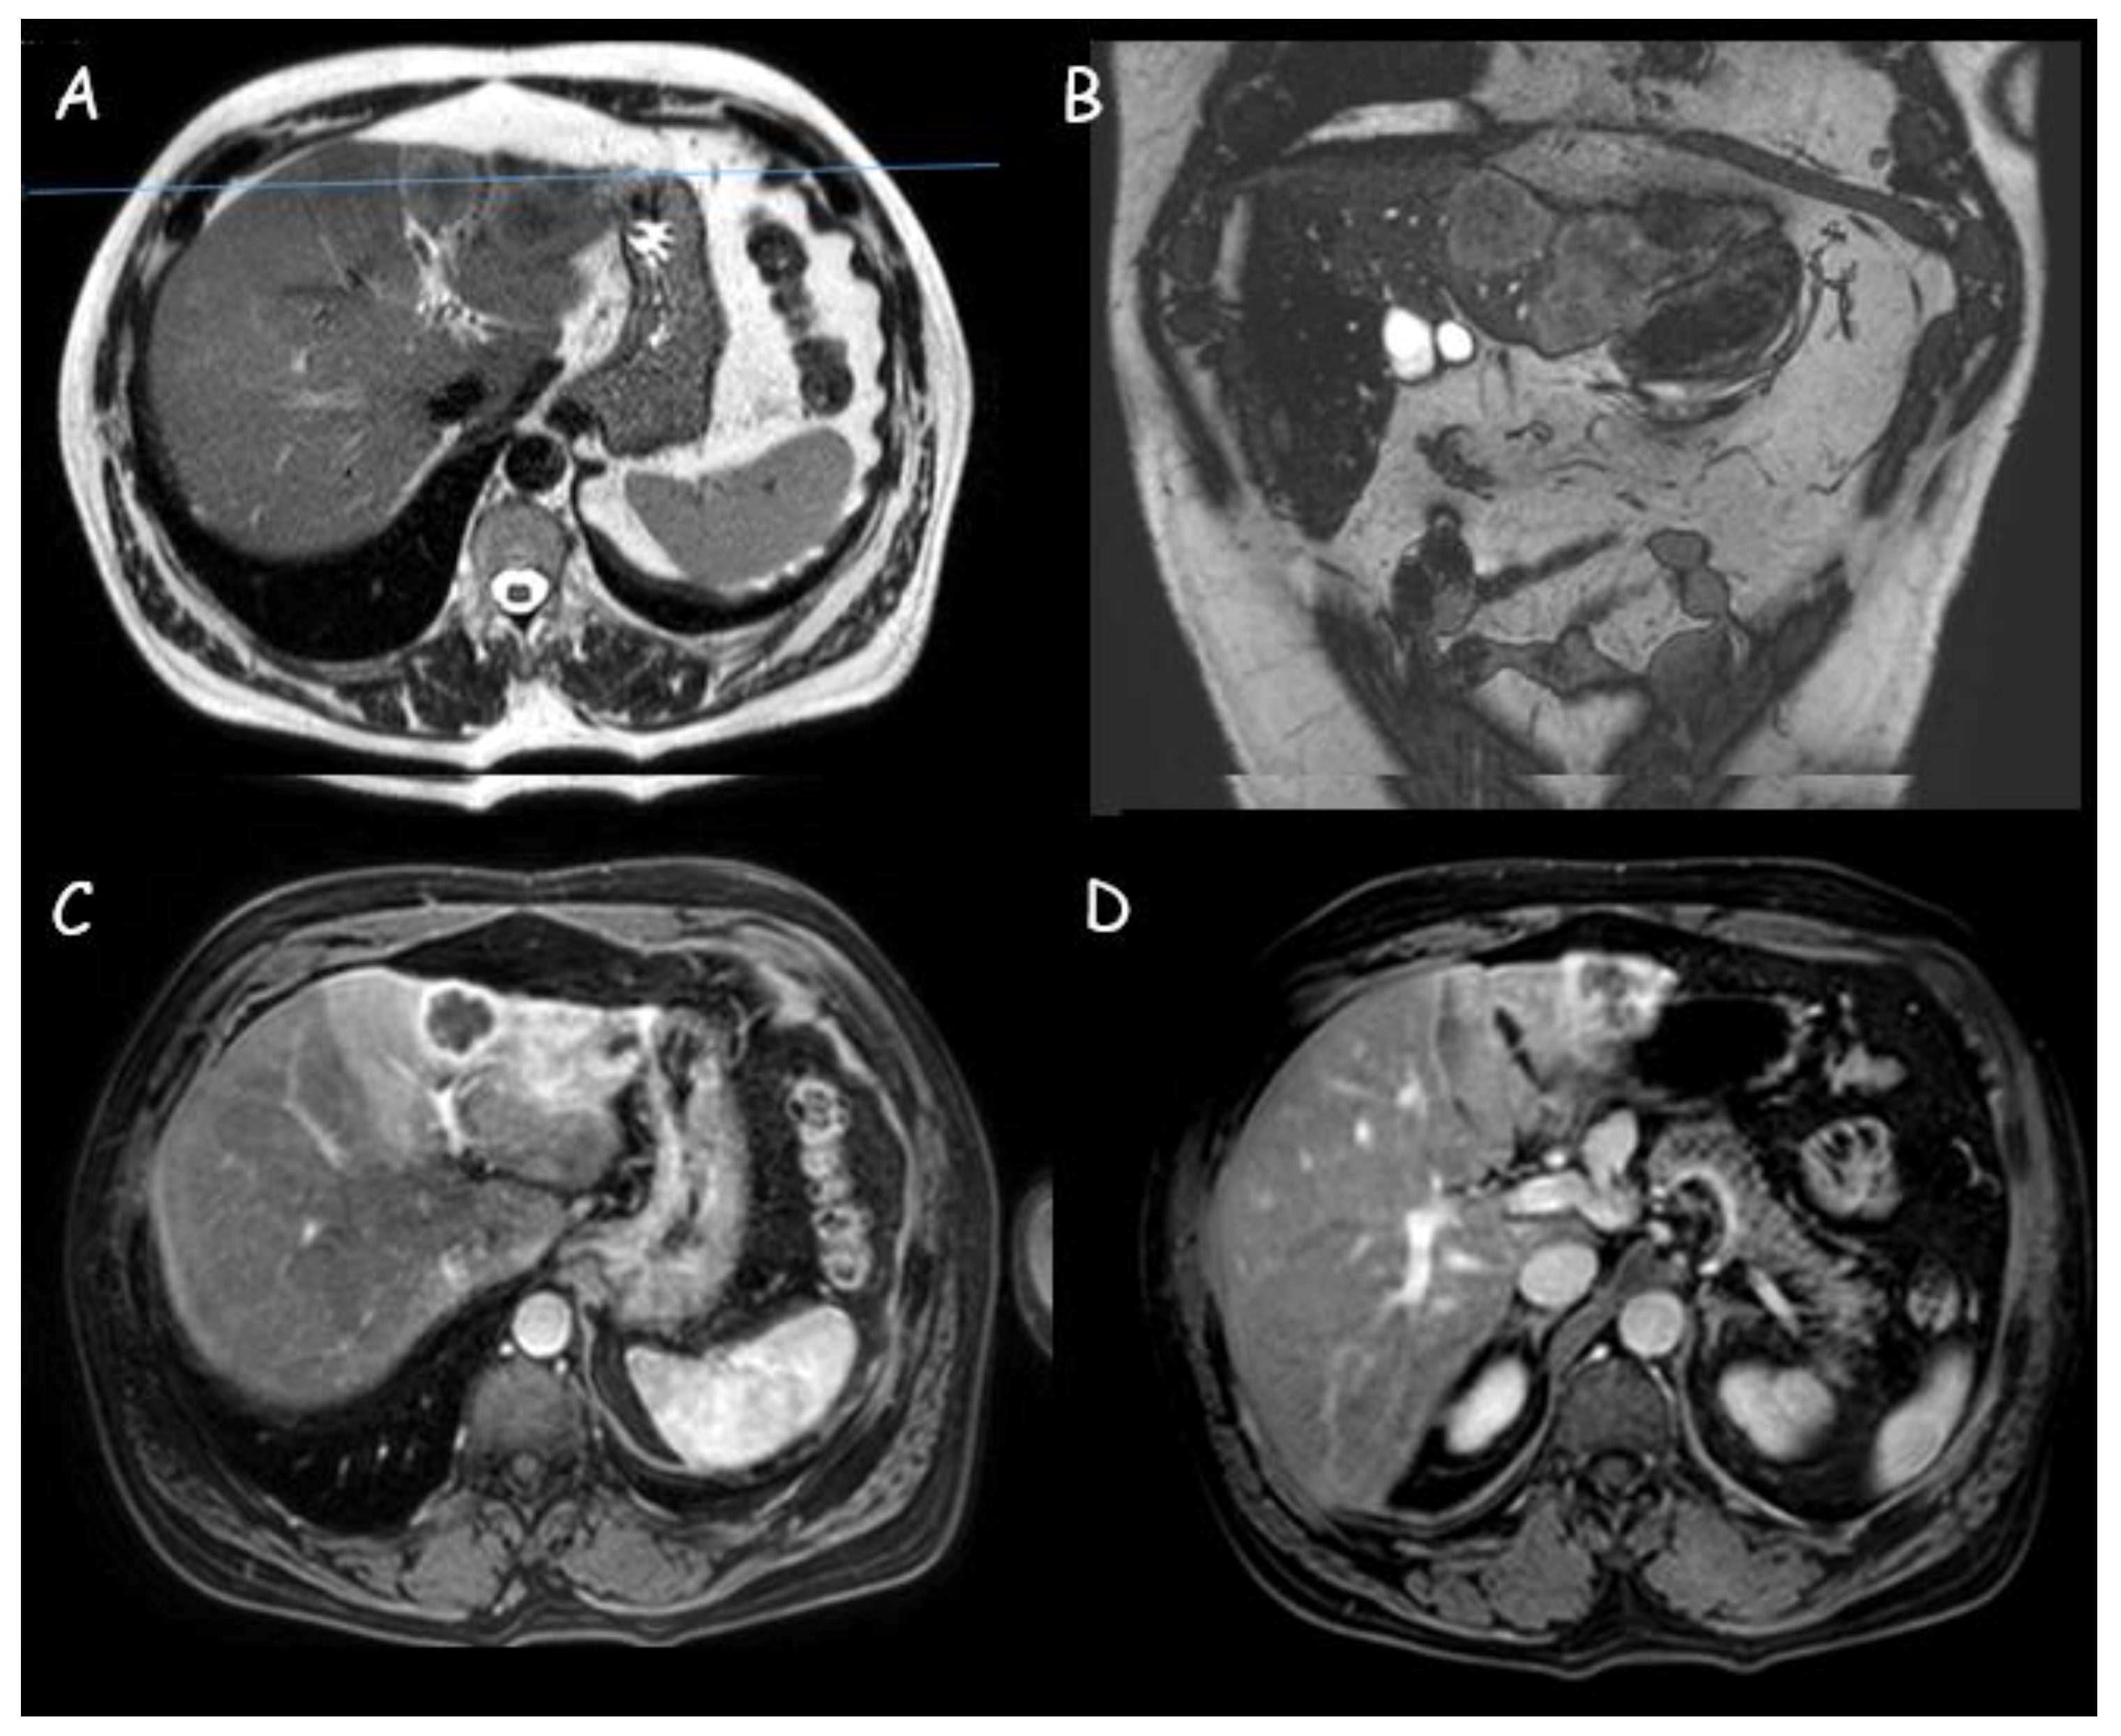

1.2. Magnetic Resonance Imaging

- Murakami, T.; Nakamura, H.; Tsuda, K.; Ishida, T.; Tomoda, K.; Hori, S.; Monden, M.; Kanai, T.; Wakasa, K.; Sakurai, M.; et al. Contrast-enhanced MR imaging of intrahepatic cholangiocarcinoma: Pathologic correlation study. J. Magn. Reson. Imaging 1995, 5, 165–170. [Google Scholar] [CrossRef]

- Ciresa, M.; De Gaetano, A.M.; Pompili, M.; Saviano, A.; Infante, A.; Montagna, M.; Guerra, A.; Giuga, M.; Vellone, M.; Ardito, F.; et al. Enhancement patterns of intrahepatic mass-forming cholangiocarcinoma at multiphasic computed tomography and magnetic resonance imaging and correlation with clinicopathologic features. Eur. Rev. Med. Pharmacol. Sci. 2015, 19, 2786–2797. [Google Scholar]

- Koh, J.; Chung, Y.E.; Nahm, J.H.; Kim, H.Y.; Kim, K.-S.; Park, Y.N.; Kim, M.-J.; Choi, J.-Y. Intrahepatic mass-forming cholangiocarcinoma: Prognostic value of preoperative gadoxetic acid-enhanced MRI. Eur. Radiol. 2016, 26, 407–416. [Google Scholar] [CrossRef]

- Kang, Y.; Lee, J.M.; Kim, S.H.; Han, J.K.; Choi, B.I. Intrahepatic Mass-forming Cholangiocarcinoma: Enhancement Patterns on Gadoxetic Acid–enhanced MR Images. Radiology 2012, 264, 751–760. [Google Scholar] [CrossRef]

- Mamone, G.; Marrone, G.; Caruso, S.; Carollo, V.; Gentile, G.; Crino’, F.; Milazzo, M.; Gianluca, M. Intrahepatic mass-forming cholangiocarcinoma: Enhancement pattern on Gd-BOPTA-MRI with emphasis of hepatobiliary phase. Abdom. Imaging 2015, 40, 2313–2322. [Google Scholar] [CrossRef]

- Xing, L.-H.; Zhuo, L.-Y.; Wang, J.-N.; Zhang, Y.; Zhu, F.-Y.; Wang, C.; Yin, X.-P.; Gao, B.-L. Values of MRI Imaging Presentations in the Hepatobiliary Phase, DWI and T2WI Sequences in Predicting Pathological Grades of Intrahepatic Mass-Forming Cholangiocarcinoma. Front. Oncol. 2022, 12, 867702. [Google Scholar] [CrossRef] [PubMed]

- Ma, X.; Liu, L.; Fang, J.; Rao, S.; Lv, L.; Zeng, M.; Shi, Y.; Yang, C. MRI features predict microvascular invasion in intrahepatic cholangiocarcinoma. Cancer Imaging Off. Publ. Int. Cancer Imaging Soc. 2020, 20, 40. [Google Scholar] [CrossRef] [PubMed]

- Min, J.H.; Kim, Y.K.; Choi, S.-Y.; Kang, T.W.; Lee, S.J.; Kim, J.M.; Ahn, S.; Cho, H. Intrahepatic Mass-forming Cholangiocarcinoma: Arterial Enhancement Patterns at MRI and Prognosis. Radiology 2019, 290, 691–699. [Google Scholar] [CrossRef]

- Jin, K.-P.; Sheng, R.-F.; Yang, C.; Zeng, M.-S. Combined arterial and delayed enhancement patterns of MRI assist in prognostic prediction for intrahepatic mass-forming cholangiocarcinoma (IMCC). Abdom. Radiol. N. Y. 2022, 47, 640–650. [Google Scholar] [CrossRef]